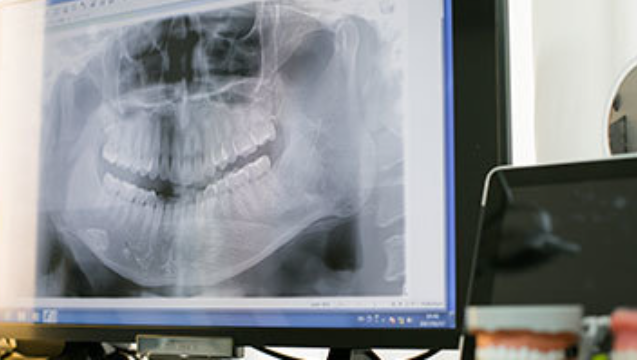

2.精密検査(約40分)

具体的な治療計画を立てるために、3DCTスキャン、写真撮影(口腔内・顔面)、3D光学カメラによる歯型取得を行い、後日診断結果をお伝えします。歯並びやかみ合わせを正確に把握するための重要なステップです。